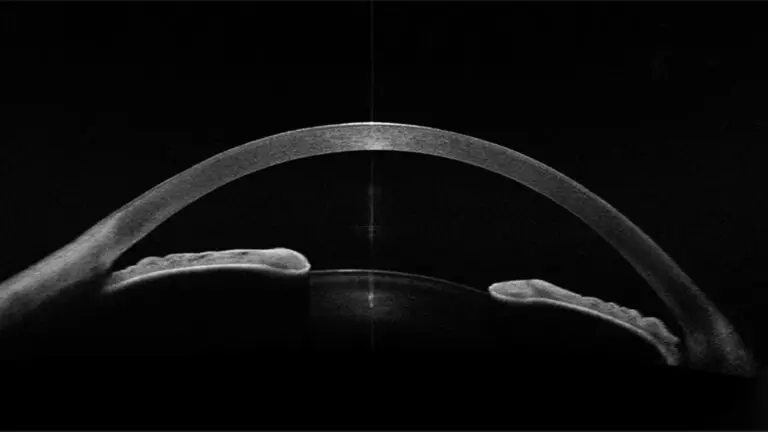

The anterior segment OCT (Optical Coherence Tomography) is a sophisticated, non-invasive imaging technology for the front (anterior) structures of the eye. Unlike traditional eye tests which provide limited two-dimensional views, this advanced scan generates high-definition, cross-sectional images of your cornea, iris, anterior chamber, and lens. It employs light waves – akin to ultrasound, but with light rather than sound – capturing incredibly detailed layers invisible to the naked eye.

A vault scan is a specialised use of anterior segment OCT, measuring the “vault” – that is, the precise space between an implanted lens (such as an ICL) and the natural lens. This distance (the vault) is vital: a vault that is too low or too high can lead to complications, making this scan indispensable for post-surgical monitoring and ongoing eye care.